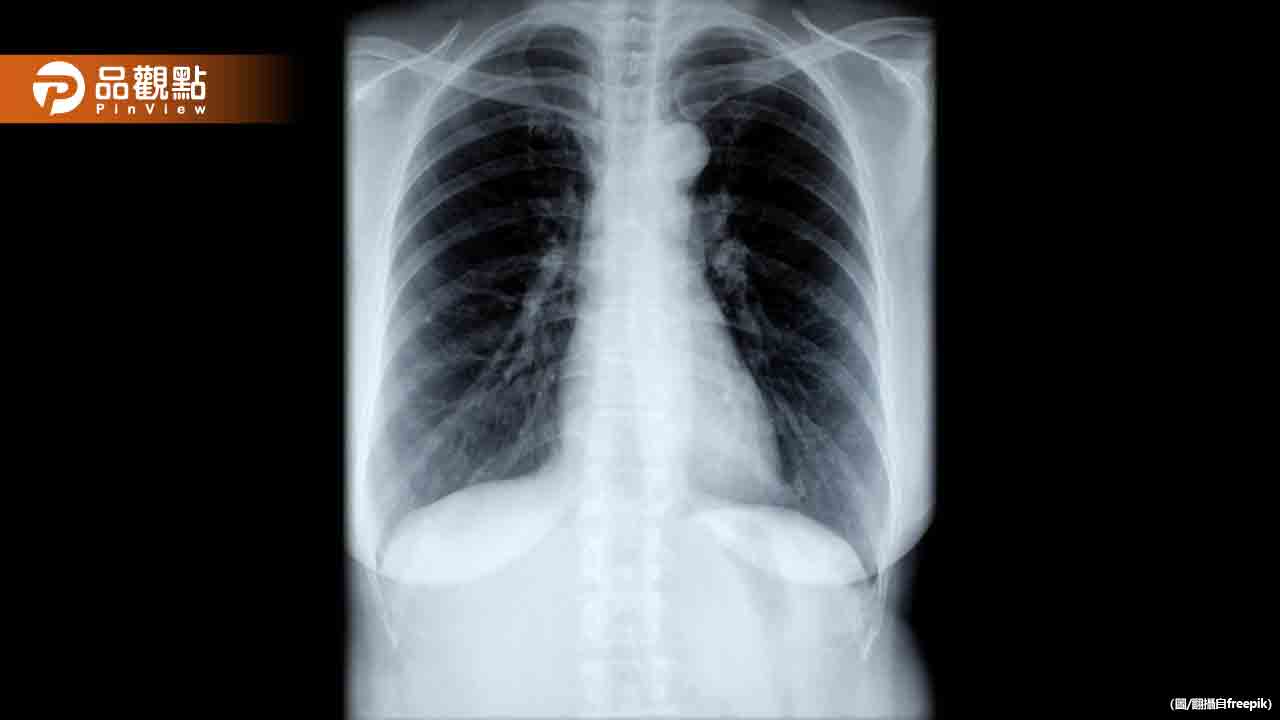

外國媒體報導,譚德塞在瑞士達佛斯世界經濟論壇上表示,武漢肺炎就是歷來第一起「X疾病」,在武肺之後為另一場傳染病做好準備很重要,由於醫療系統的不足,全球有很多武肺患者在疫情時去世,透過WHO大流行病協議,能有效地幫助各國更好地應對未來疫情。

據報導指出,新冠肺炎疫情過去3年多來,在全球已造成近7億人感染、將近700萬人死亡。世衛組織採用「X疾病」一詞,來代表假設性的疾病,可能由已知或未知病原體引起,且隨時可能爆發,構成重大公衛風險,有待進一步研究與監測。